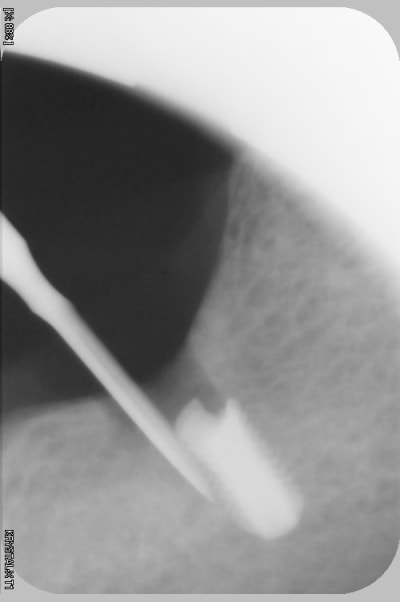

l'erreur vient dans ce cas pas du guide mais de mon inexpérience, le maillon faible ( de RENOUARD) c'est moi.

et là mauvaise nouvelle, j'ai voulu sortir l'implant , mais l'implant s'en va pour trois mois. va falloir sortrir la fraise à os, l'insert diamanté, et les loupes

à mon avis tu augmenter fortement tes problèmes si tu attends 3 mois, l'os peut se reformer et tu ne trouveras plus ton implant.... si tu stress trop avec le patient, fais toi assister par un confrère le patient ne t'en voudra pas.

2 solutions: soit retirer l'implant soit faire une empreinte et faire faire un pilier long (titane) lisse qui va transformer ton implant en transosseux/transmuqueux... si tu n'as pas de ciment pour la jonction c'est tout à fait jouable.

soit tu t'amuse à l'enlever (le plus simple est de trouver un outil long et de dévisser, ou bien: le trépan....

oui finalement, lambeau , j ai enlevé de l os à la fraise, puis à la fin avec un insert à boule diamantée, pour finir sans abîmer la tête de vis ( conseil que j avais lu sur eugenol). Puis j ai mis une grosse vis de cicat.

Trois semaines plus tard j ai fait mon empreinte puis mis la couronne scellée (,cvimar) sur pilier vissé